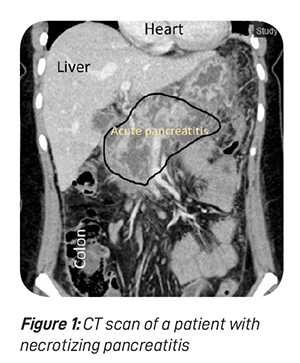

Necrosis means dead or non-viable. When a part of the pancreas or surrounding fatty tissue is dead due to severe and extensive inflammation, necrotising pancreatitis is diagnosed (see figure 1). The treatment of necrotising pancreatitis involves additional consideration for the treatment of necrotic tissue.

In olden times, urgent surgery would have been advocated. However, modern understanding dictates that doing “less is more”. If a patient’s condition is reasonably stable, any intervention is generally not advocated in order to balance between risk and gain. Interventional radiology specialists may place a “drainage tube” in and around the pancreas, if necessary, to aid in the drainage of the dirty effluent outside the body cavity. Most patients will improve with this procedure.